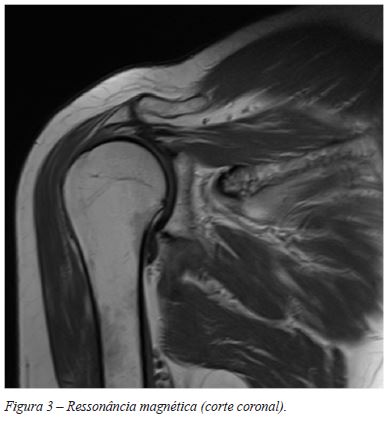

A Ressonância Magnética (RMN), apesar de não ser um meio complementar diagnóstico específico para esta patologia, é útil no sentido em que permite diferencia-la de outras patologias articulares e estratificar a extensão da doença. A RMN trata-se de um método de diagnóstico não invasivo, que detecta as lesões difusas e infiltrativas dos tecidos moles, hipodensas em T1 e T2. A hemossiderina causa diminuição de sinal em T1 e T26.

A RMN que mostrou alterações degenerativas da articulação acrómio-clavicular e articulação gleno-umeral, rotura do músculo supra-espinho (SPP) e sinais sinovite com hiposinal, tanto em T1 como em T2, sem invasão extra-articular (Figuras 3 e 4). Optou-se pelo para tratamento cirúrgico artroscópico.